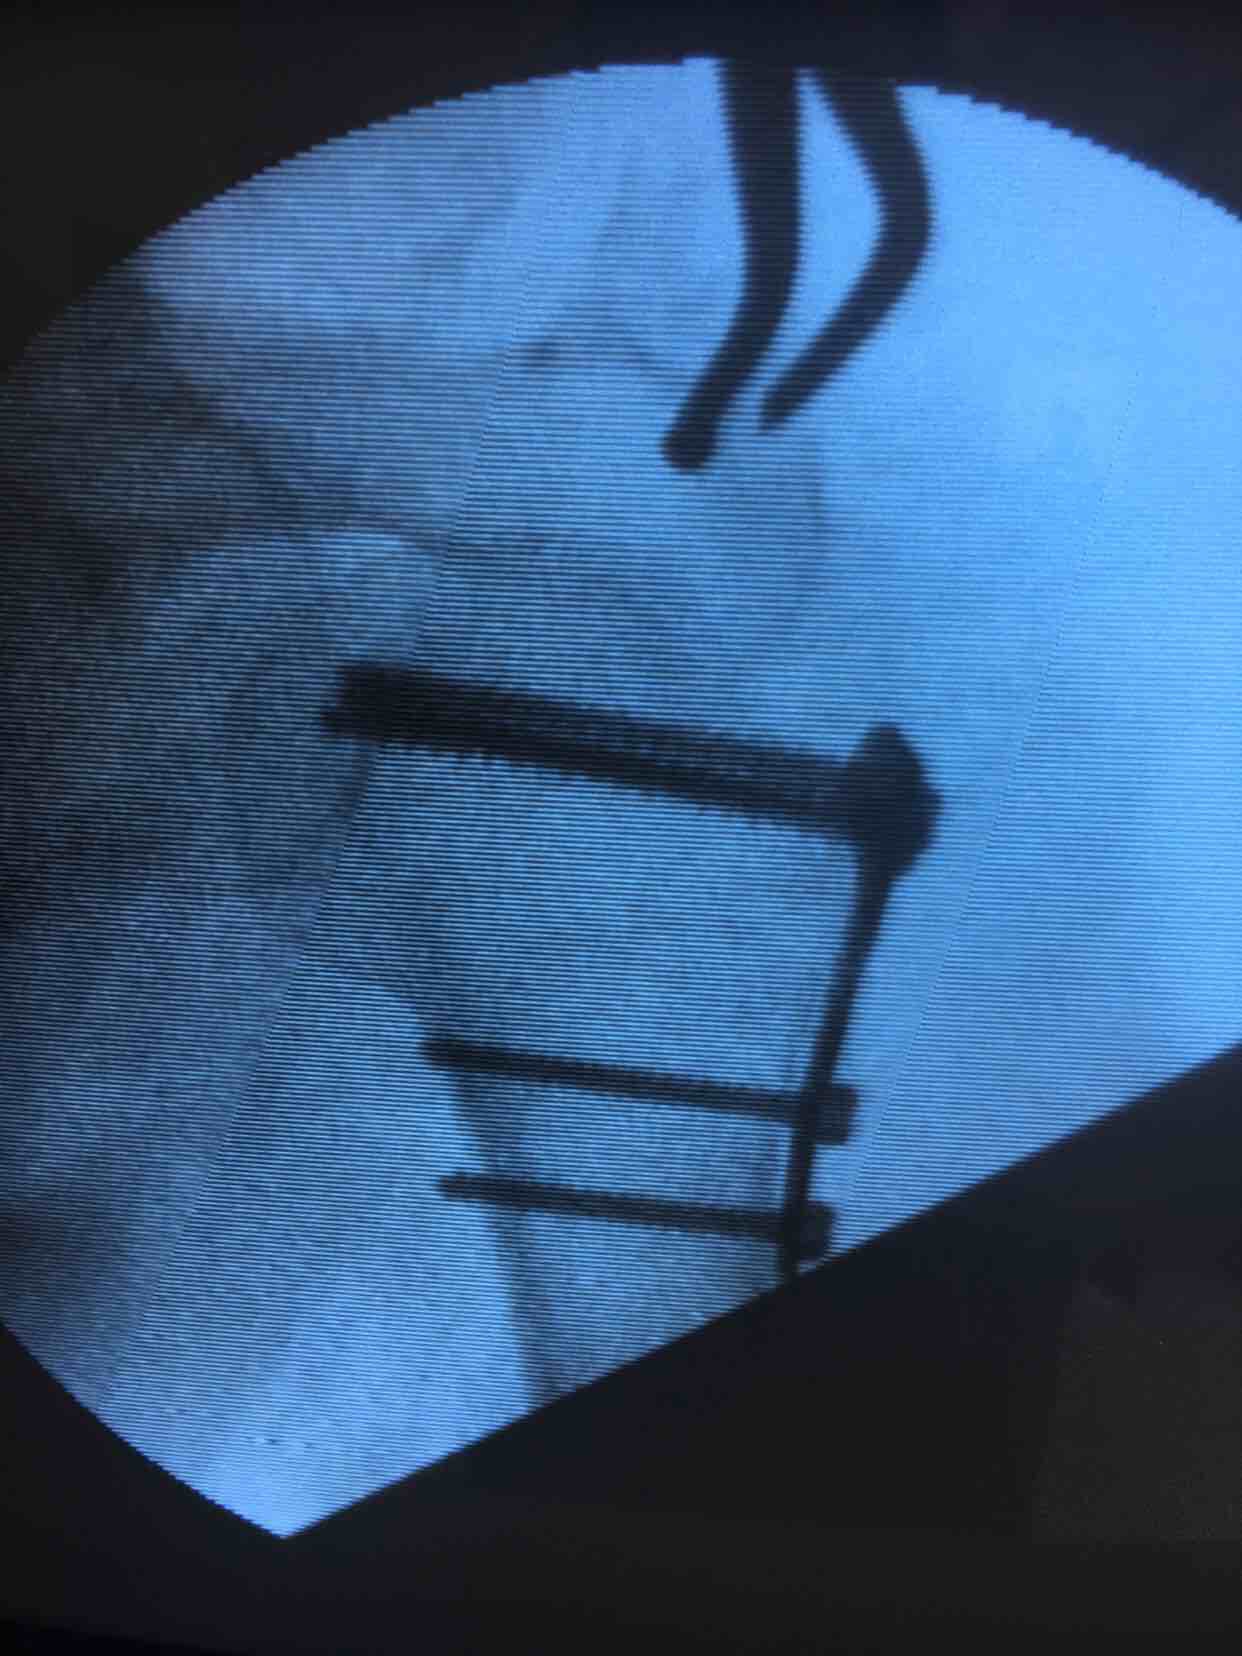

肩关节脱位并大结节骨折(切复内固定)

诊断肩关节脱位并大结节骨折在臂丛麻醉下行切复内固定术,术后外展架固定,抗炎,消肿等处理。